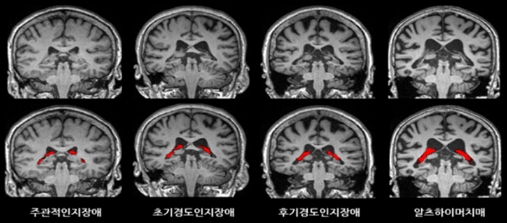

건국대병원 영상의학과 문원진 교수 연구팀은 다양한 정도의 인지저하가 있는 환자 532명을 대상으로 3Tesla 뇌 MRI 사진을 분석했다. 이 중 132명의 환자에게서는 역동적조영증강영상(DEC 영상)을 이용해 투과도 영상을 얻었다. 연구 대상자 중 알츠하이머 치매를 앓고 있는 환자는 147명이었다.

분석 결과, 알츠하이머 치매 환자의 맥락얼기 부피가 정상인보다 더 큰 것으로 확인됐다. 맥락얼기의 부피가 클수록 기억력과 자기통제, 기억력을 관장하는 광범위한 정신능력인 실행기능(executive function)이 저하된 것으로 나타났다. 맥락얼기의 투과성은 경도인지장애에 비해 알츠하이머에서 낮아진 것으로 확인됐다.

문 교수는 “뇌 깊은 곳에는 학습과 기억에 중요한 역할을 하는 ‘해마(hippocampus)’라 불리는 구조물이 존재하는데, 현재까지 알츠하이머 치매 진단에 있어 MRI의 역할은 신경퇴화(neurodegeneration)의 일환으로 해마의 위축을 보여주거나 혈관성 병변을 감지하는 데 국한돼 있었다”며, “이번 연구 결과는 맥락얼기의 이상(혈액-뇌척수액장벽의 이상)을 MR영상으로 보여줄 수 있다는 새로운 가능성을 시사했다는 점에서도 의의가 있다”고 설명했다.

문 교수는 “이번 연구에 대해 선별 검사 단계에서 맥락얼기 부피와 해마 부피를 함께 평가한다면 알츠하이머 치매에 ‘더 취약한 환자’와 ‘덜 취약한 환자’를 구분할 수 있을 것”이라며 “병이 진행됨에 따라 맥락얼기의 부피가 어떻게 변하는지에 대한 종단연구(longitudinal study)를 진행 계획”이라고 밝혔다.